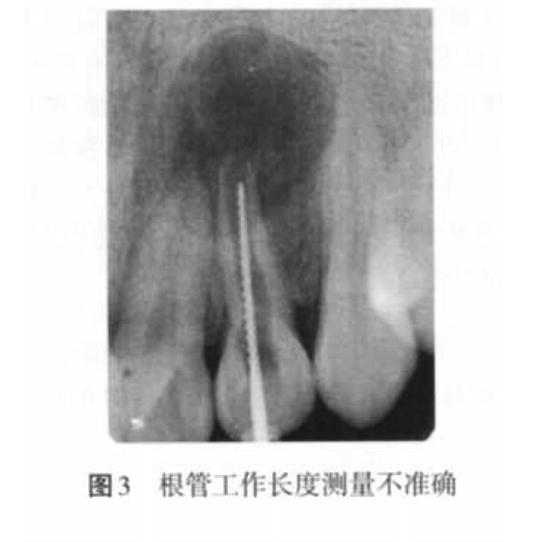

2. 2 充填止點不當(dāng)?shù)脑?p style="text-indent: 2em; text-align: left;">(1)欠充原因:當(dāng)根管預(yù)備不足、根管工作長度測量不準確(圖 3)、主牙膠尖選擇不合適、根充技術(shù)選擇不當(dāng)以及術(shù)者操作不當(dāng)時,均可以導(dǎo)致欠充發(fā)生。